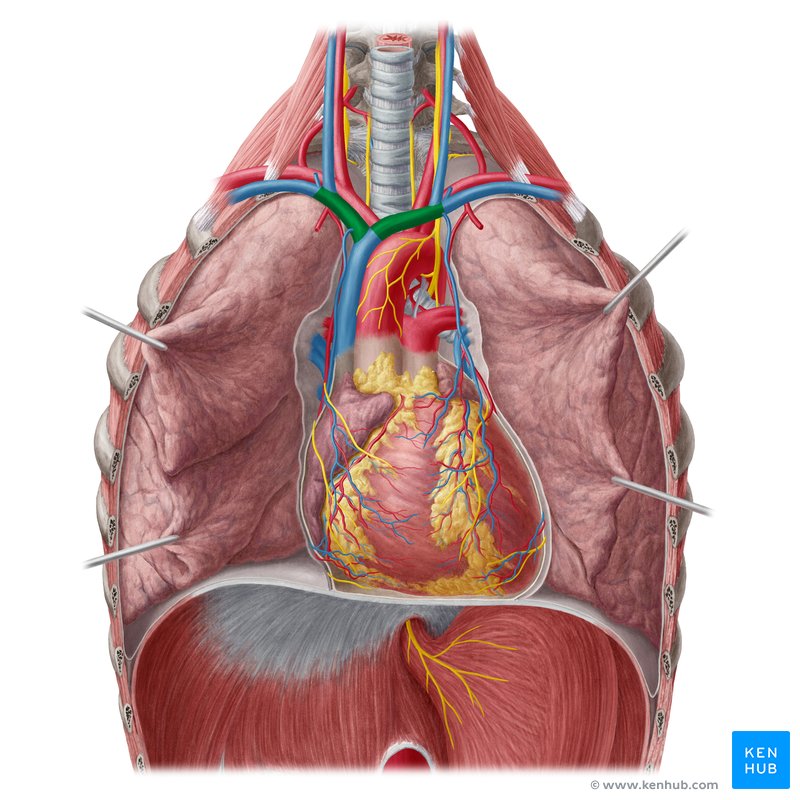

Left Atrium

Right Atrium

Left Ventricle

Right Ventricle

Inferior Vena Cava

Superior Vena Cava

Pulmonary Trunk

Subclavian Artery

Anterior Interventricular Artery

Circumflex Branch

Coronary Artery

Common Carotid Artery

Aortic Arch

Brachiocephalic Trunk

Thoracic Aorta

Pulmonary Artery

Pulmonary Vein